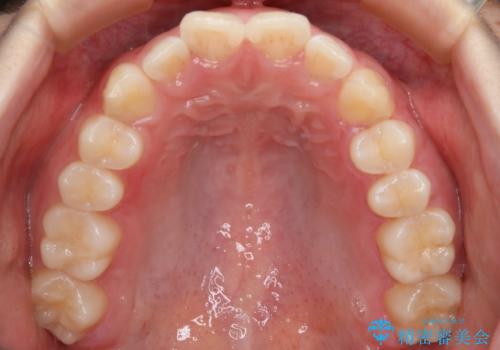

- 前歯のガタつきの改善を主訴に来院された患者様です。

ガタつきによる上顎正中の空隙や歯の突出感も気にされていました。

費用を抑えたいとの事だったので歯の移動量なども考慮し、インビザライン・ライトパッケージでの治療を計画しました。